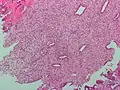

Adénocarcinome endométrioïde, vue d'une biopsie. Coloration HE.